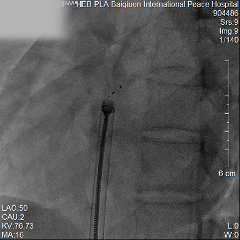

手术过程

左盘展开

右盘展开

牵拉试验

释放封堵器

封堵器最终形态